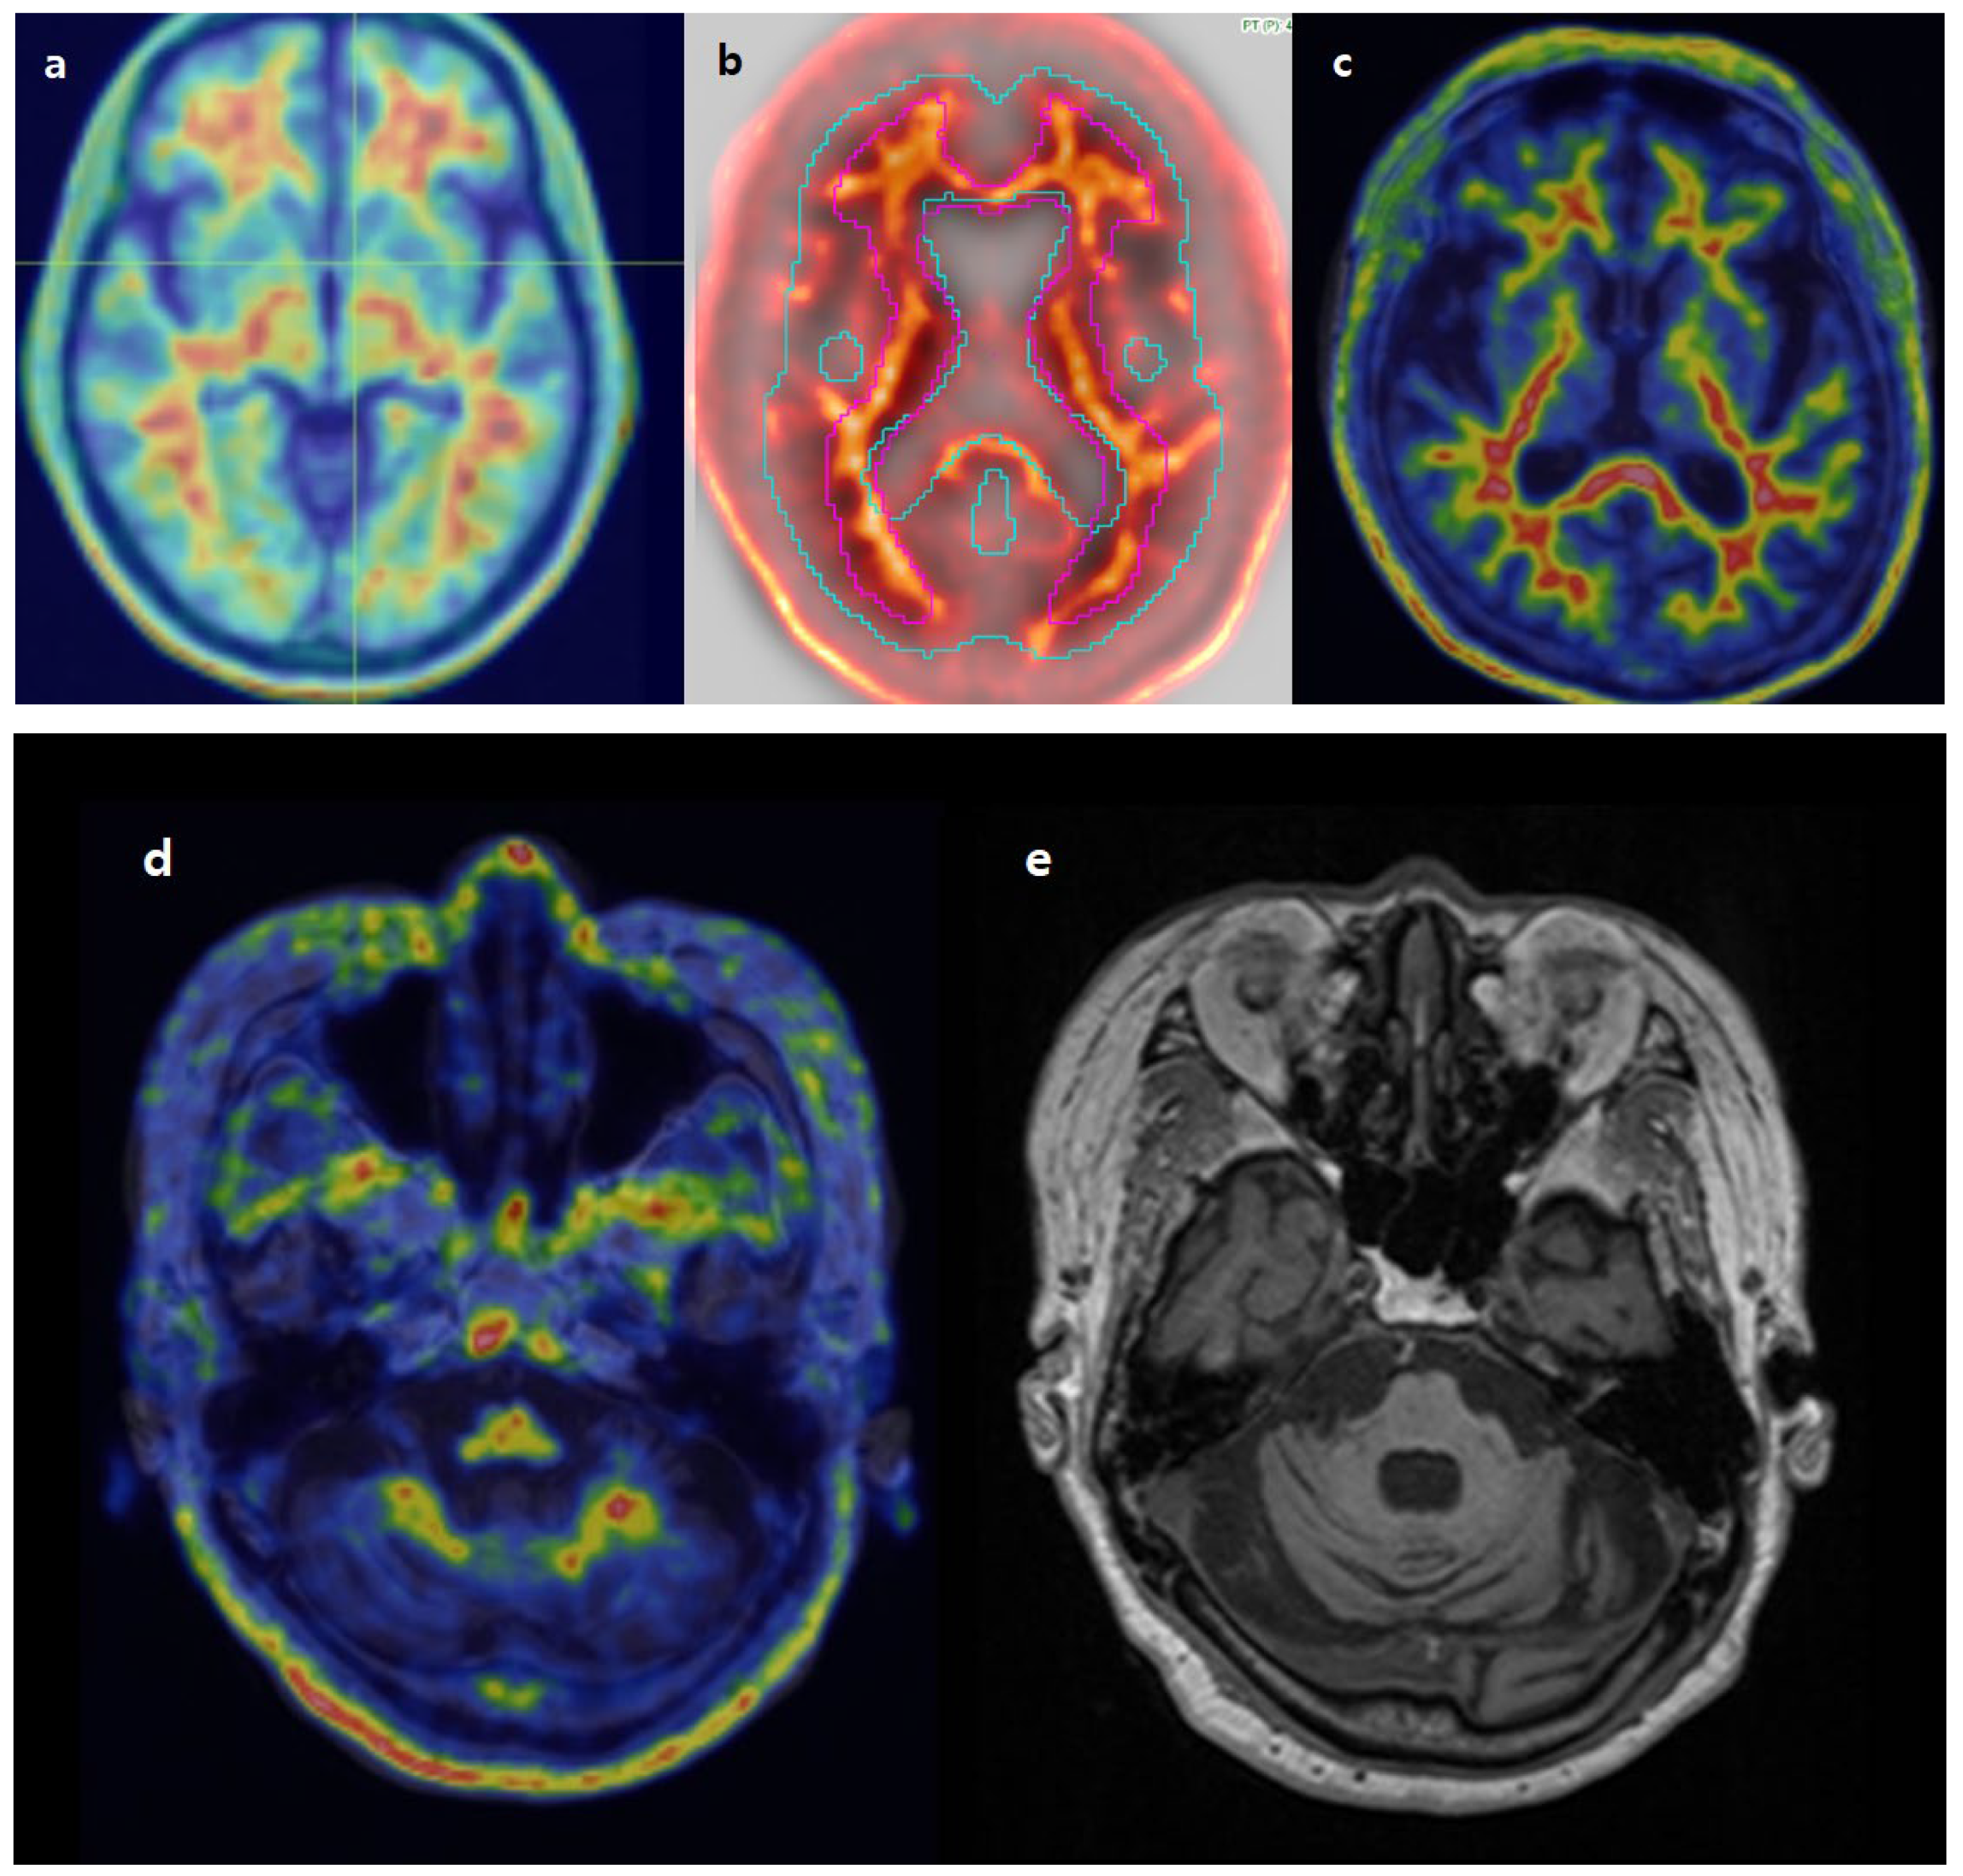

3.2. Image Analysis

3.6. Review of Individual Discordant Cases